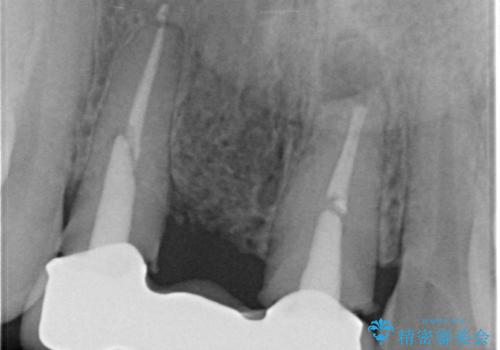

現在装着されているブリッジを除去したところ、歯ぐきよりも上に存在する歯質(縁上歯質)が少なく、土台の形態の悪さや不適合などさまざまな問題があります。

根管治療を行ったのち、歯周外科を行うことで、欠損部の歯ぐきの厚みを出し、縁上歯質を獲得することで、長期的な予後の見込めるブリッジを製作できる環境を整備していきます。